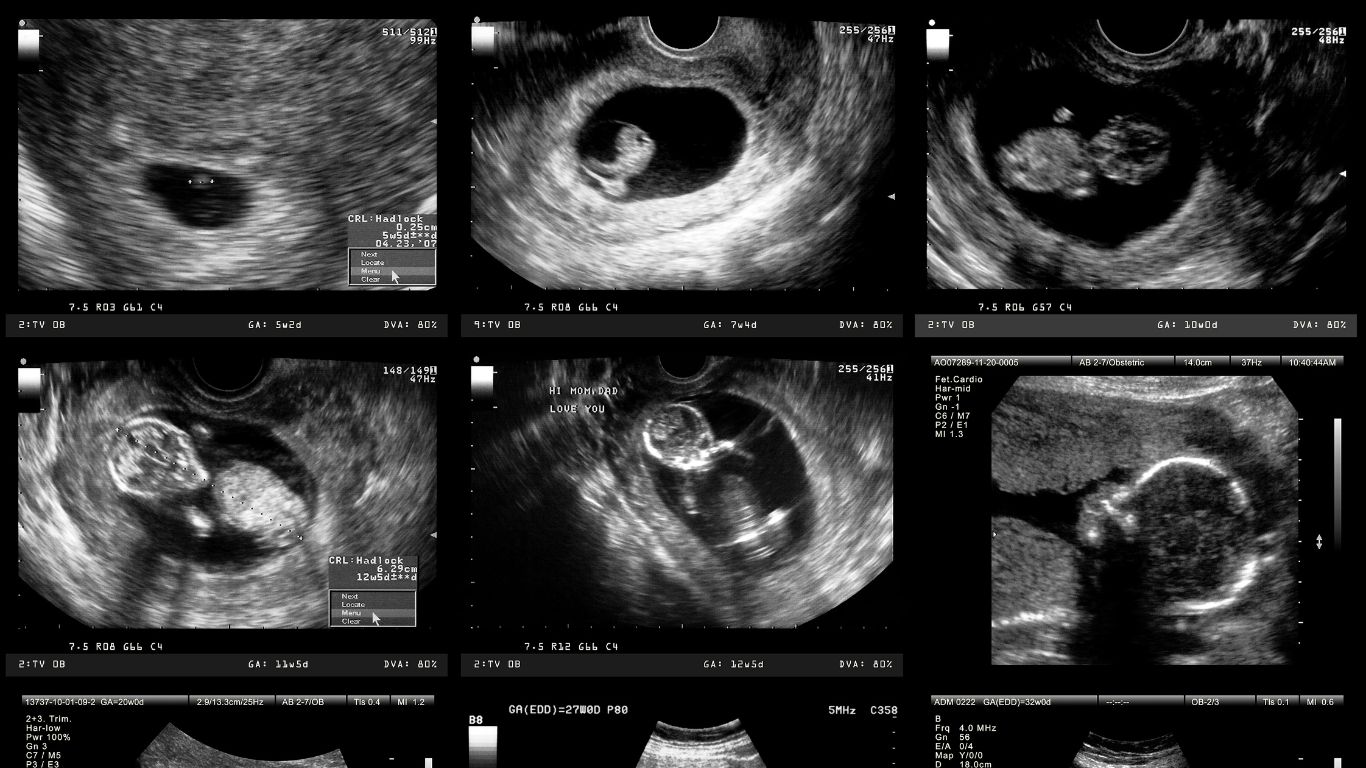

El ultrasonido estructural, también conocido como ecografía estructural, es un procedimiento esencial en el ámbito del diagnóstico prenatal. Este examen utiliza ondas sonoras para formar imágenes detalladas del feto, lo que permite observar de cerca los órganos y estructuras en desarrollo. Su propósito principal es identificar cualquier posible anomalía desde etapas tempranas del embarazo, facilitando así una atención prenatal más eficiente.

La ecografía estructural se lleva a cabo, típicamente, entre la semana 18 y 22 de gestación. Este tipo de ultrasonidos no solo se centra en la visualización del feto, sino que también examina la placenta y el líquido amniótico. Al abordar estos aspectos, el examen busca detectar anomalías congénitas y asegurar que el embarazo se desarrolle dentro de parámetros saludables.

Este ultrasonido se realiza entre las semanas 6 y 12 de gestación. Tiene como objetivo confirmar el embarazo, así como determinar el número de fetos presentes. También permite observar la actividad cardíaca fetal, lo que representa un avance significativo en el seguimiento del desarrollo fetal.

El ultrasonido del segundo trimestre se lleva a cabo entre las semanas 18 y 22. Este procedimiento brinda una evaluación anatómica completa del feto. Durante esta etapa, se pueden identificar anomalías físicas que necesitan atención. La detección temprana de estos problemas facilita la planificación del cuidado necesario para el desarrollo fetal.

Por último, el ultrasonido del tercer trimestre, realizado entre las semanas 28 y 36, se centra en monitorear el crecimiento y la posición del bebé. Este examen se convierte en un pilar importante para asegurar un parto seguro y saludable. Conocer la posición del feto ayuda a las madres a prepararse adecuadamente para el evento del nacimiento.